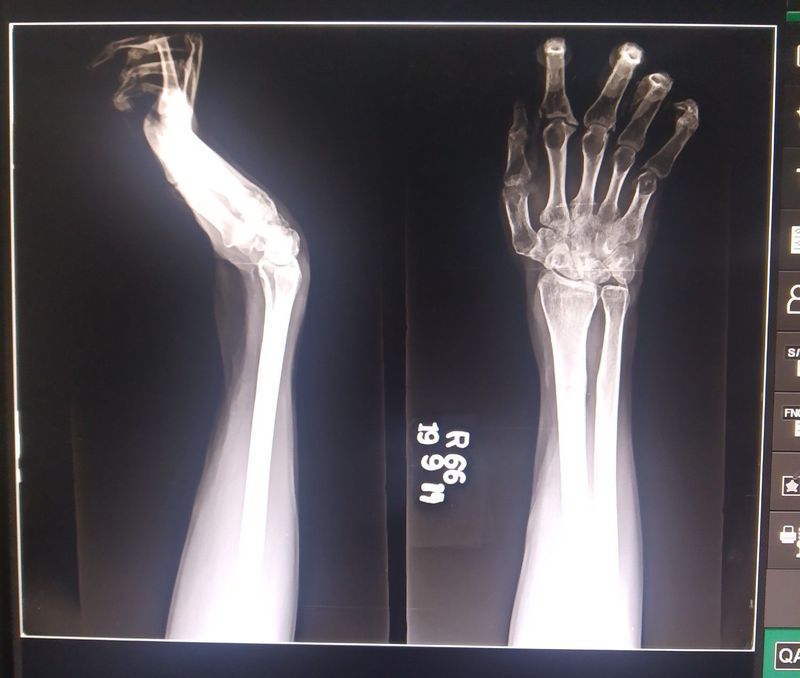

Any guesses for this x-ray of hand AP and oblique??

Claw hand deformity? Result of ulnar nerve damage.. paralysed lumbricals

Yes ! it's a claw hand deformity

Ulnar claw hand?